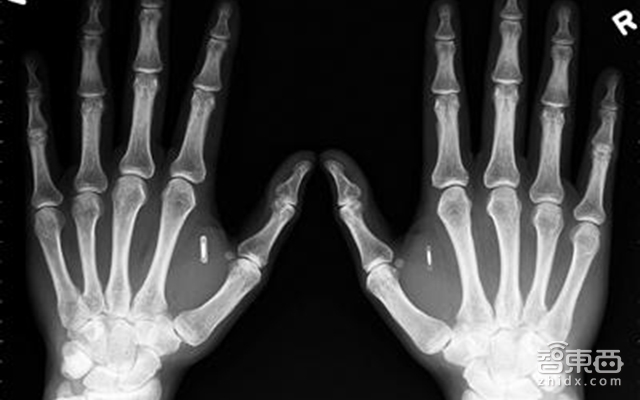

1、比利时公司为员工植入芯片

2月8日报道,比利时一家名为“新融合”的公司向员工手中植入可识别芯片,其中包含个人信息,并能访问公司的智能系统。目前可确认全球范围内已有约1万人被植入此类芯片,这款备受争议的设备已在个人隐私和安全领域引发讨论。

芯片长约3厘米,宽度与铅笔芯差不多,外表像一粒大米。人们可以在线购买植入试剂盒,盒子里包括无菌注射器,带有预加载的芯片和用于伤口护理的纱布。人们直接通过针管就能将芯片注射到拇指和食指之间的肌肉组织中。

这款RFID芯片被设置为可适用于一系列应用程序,甚至允许直接启动汽车。专家介绍说,芯片能给出一个清单,列出用户今天要做的事情,如同一个私人数据系统,通知你接下来几个小时要做什么。但也有人认为它对信息安全造成了威胁,至少要赶在政府机构或谷歌、脸谱网等大公司前来推销产出的芯片前,全面知晓植入芯片对个人信息安全的影响。